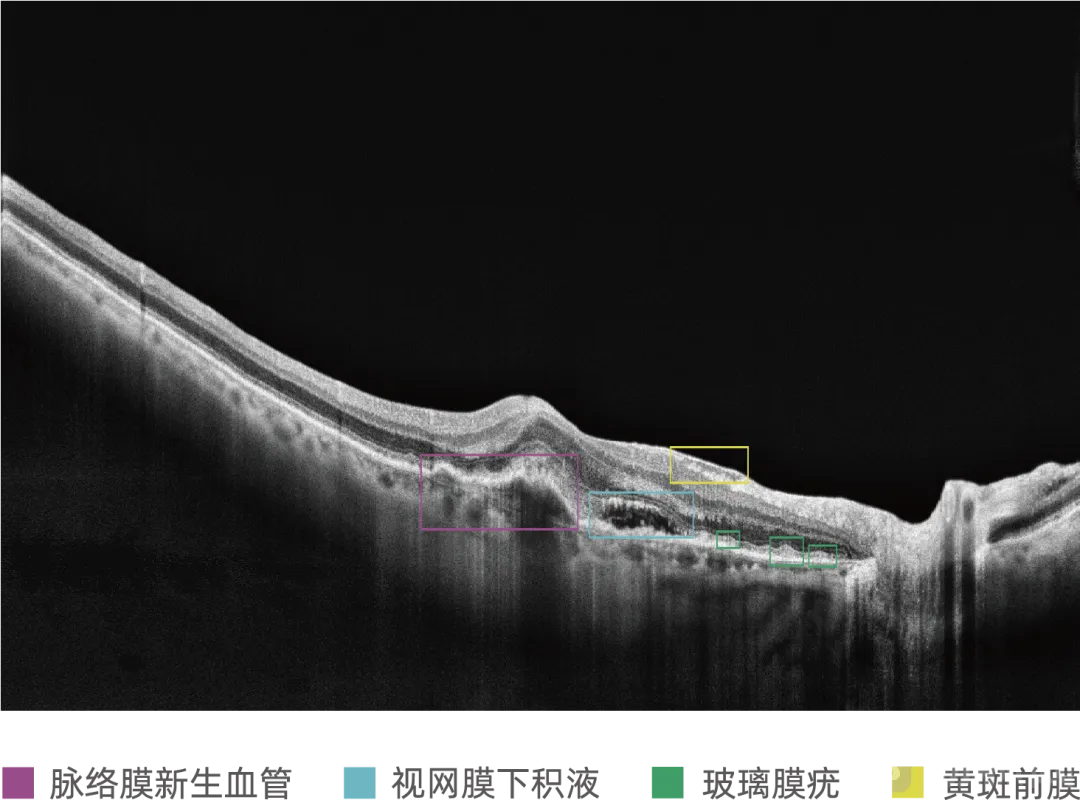

近日,电子科技大学、苏州大学、汕头大学·香港中文大学联合汕头国际眼科中心和新加坡科技研究局等机构的研究团队开发了一种名为多标签OCT报告生成器(MORG)的深度学习模型...

医学院陈新建教授团队获得全球首张医用OCT AI三类证

2025-11-01

10月27日,医学院陈新建教授团队自主研发的眼科OCT图像辅助诊断软件MIAS-3000正式获得国家药品监督管理局三类医疗器械注册证(注册证号:20253212107),成为全球首款获批三...